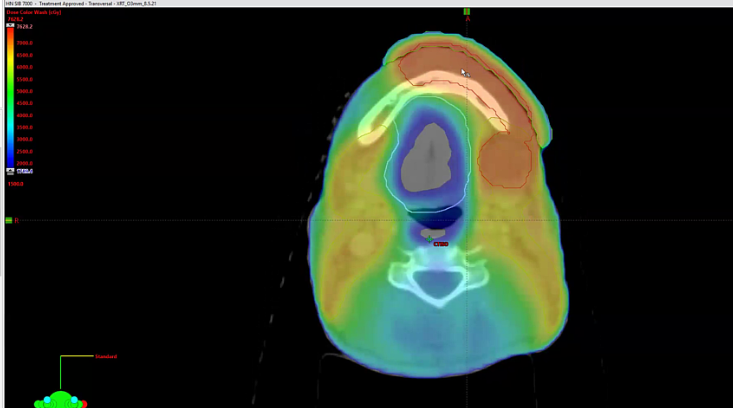

dosimetry, ipsilateral radiotherapy, randomized study, bilateral radiotherapy, cisplatin, linac, linear accelerator, Armenia, toxicity, neutropenia, gastrostomy, odynophagia, dysphasia, dehydration, anemia, blood transfusion, kidney function, SIB, symmetrical boost, sequential boost, contouring, ...